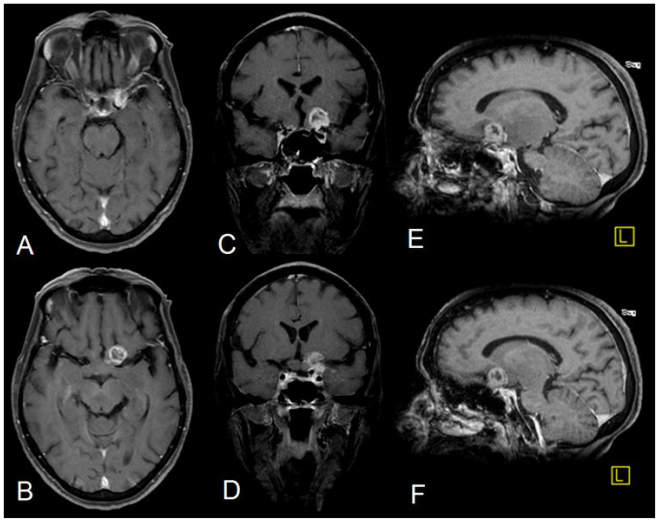

后對(duì)比圖像(使用20ml的Gadodiamide,OMNISCAN,GE Healthcare)顯示出一個(gè)小的(14×12mm)異質(zhì)環(huán),增強(qiáng)了左側(cè)視交叉上方的焦點(diǎn)(圖3)。病變的其余部分未顯示出顯著的增強(qiáng)(圖4)。然而,在左顳區(qū)觀察到微妙的腦膜增強(qiáng)。

圖3

68歲女性患有視神經(jīng)膠質(zhì)母細(xì)胞瘤。后對(duì)比T1W(TR = 845,TE = 9,SL 5mm)軸向(A和B),冠狀(TR = 825,TE = 11,C&D)和下垂。(TR = 825,TE = 9,E&F)注射20cc 0.3mmol / kg Gadodiamide(OMNISCAN,GE醫(yī)療保?。┖螅@示小的異質(zhì)環(huán)增強(qiáng)焦點(diǎn),在左側(cè)視神經(jīng)上方,左側(cè)顳側(cè)腦膜增強(qiáng)。在視神經(jīng),束和通路中沒有看到增強(qiáng)。